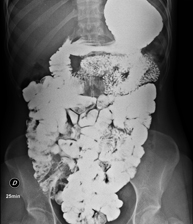

Tècnica que usa els raigs X a través de la qual s'obtenen imatges de l'abdomen (estómac, intestí prim, intestí gros, fetge, ronyons, bufeta, pelvis òssia, etc.) per al seu estudi. - RX Columna lumbar

Prova diagnòstica que consisteix en obtenir imatges radiològiques en moviment de l'esòfag, estómac i duodè mitjançant l'ús de raigs X (fluoroscòpia) i d'un contrast opac baritat que s'administra per via oral. - Trànsit intestinal

Prova diagnòstica que consisteix en obtenir imatges radiològiques en moviment de l'esòfag, estómac, duodè i intestí prim mitjançant l'ús de raigs X (fluoroscòpia) i d'un contrast opac baritat que s'administra per via oral. - Ènema opac doble contrast

Prova diagnòstica que consisteix en obtenir imatges radiològiques de l'intestí gros (còlon i recte) mitjançant l'ús de raigs X. S'utilitza un contrast opac que s'administra a través del recte en forma d'ènema i també s'introdueix aire per expandir el còlon.